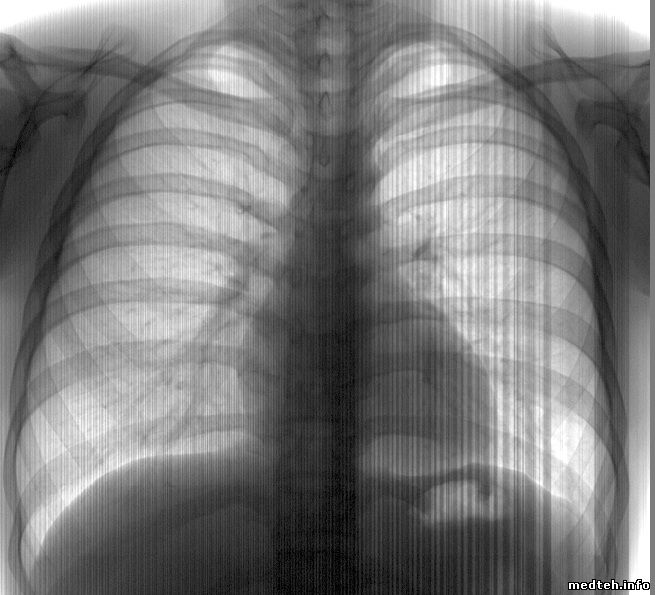

Уважаемые коллеги, столкнулся со следующей проблемой на Проскан 2000 (2010 г.в.).

С недавнего времени снимки время от времени (к сожалению закономерность выявить не удалось пока) имеют переставленный верх и низ - т.е., верхняя часть картинки может уйти вниз и таким образом "склеиться". Это происходит на прямой проекции. На боковой проекции аналогичным характером проявляются "шумы" или что-то ещё - самого снимка становится не видно.

8174406.jpg (36.3 Kb) · 9259358.jpg (124.3 Kb)